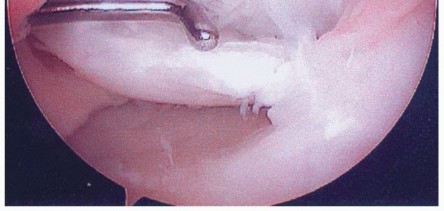

Unstable lesions have fibrous tissue and a sclerotic bony rim behind them that is best removed to allow healing to occur (

FIG 8

). Furthermore, any joint fluid beneath a

fragment will prevent formation of a fibrin clot, thereby preventing the first step necessary for bony healing.

FIG 8 • Arthroscopic image of medial femoral condyle OCD lesion. The probe is used to hinge the lesion open, demonstrating fibrous tissue beneath lesion.